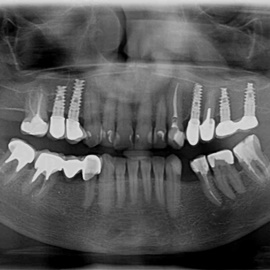

Lat 50, pół roku przed rozpoczęciem leczenia implantologicznego przestał palić papierosy. Znacząca poprawa higieny, pacjent silnie zmotywowany. Po regeneracji kości i rekonstrukcji tkanek miękkich odbudowa sześciu zębów na koronach porcelanowych. Na zdjęciu widoczna ilość i jakość tkanki kostnej po rekonstrukcji. W porównaniu ze stanem początkowym uzyskano znaczącą poprawę warunków kostnych nie do osiągnięcia metodami sterowanej regeneracji kości z użyciem reklamowanych markowych błon kolagenowych i dosypaniem kości z butelki.

Pacjent z długą historią leczenia implantologicznego. Pierwsze implanty w pozycjach 23, 24 miał wkręcane w Warszawie przed 25 laty. Implant w pozycji górnego prawego kła ma agresywny gwint, ponieważ bezpośrednio po implantacji był obciążony (immediate loading) tymczasowym atachmentem ball abutmentv do stabilizacji tymczasowej protezy ruchomej. Kość szczęki regenerowana i odbudowywana etapami w całym górnym prawym kwadrancie. Pacjent planuje uzupełnić brakujące zęby 25, 26.